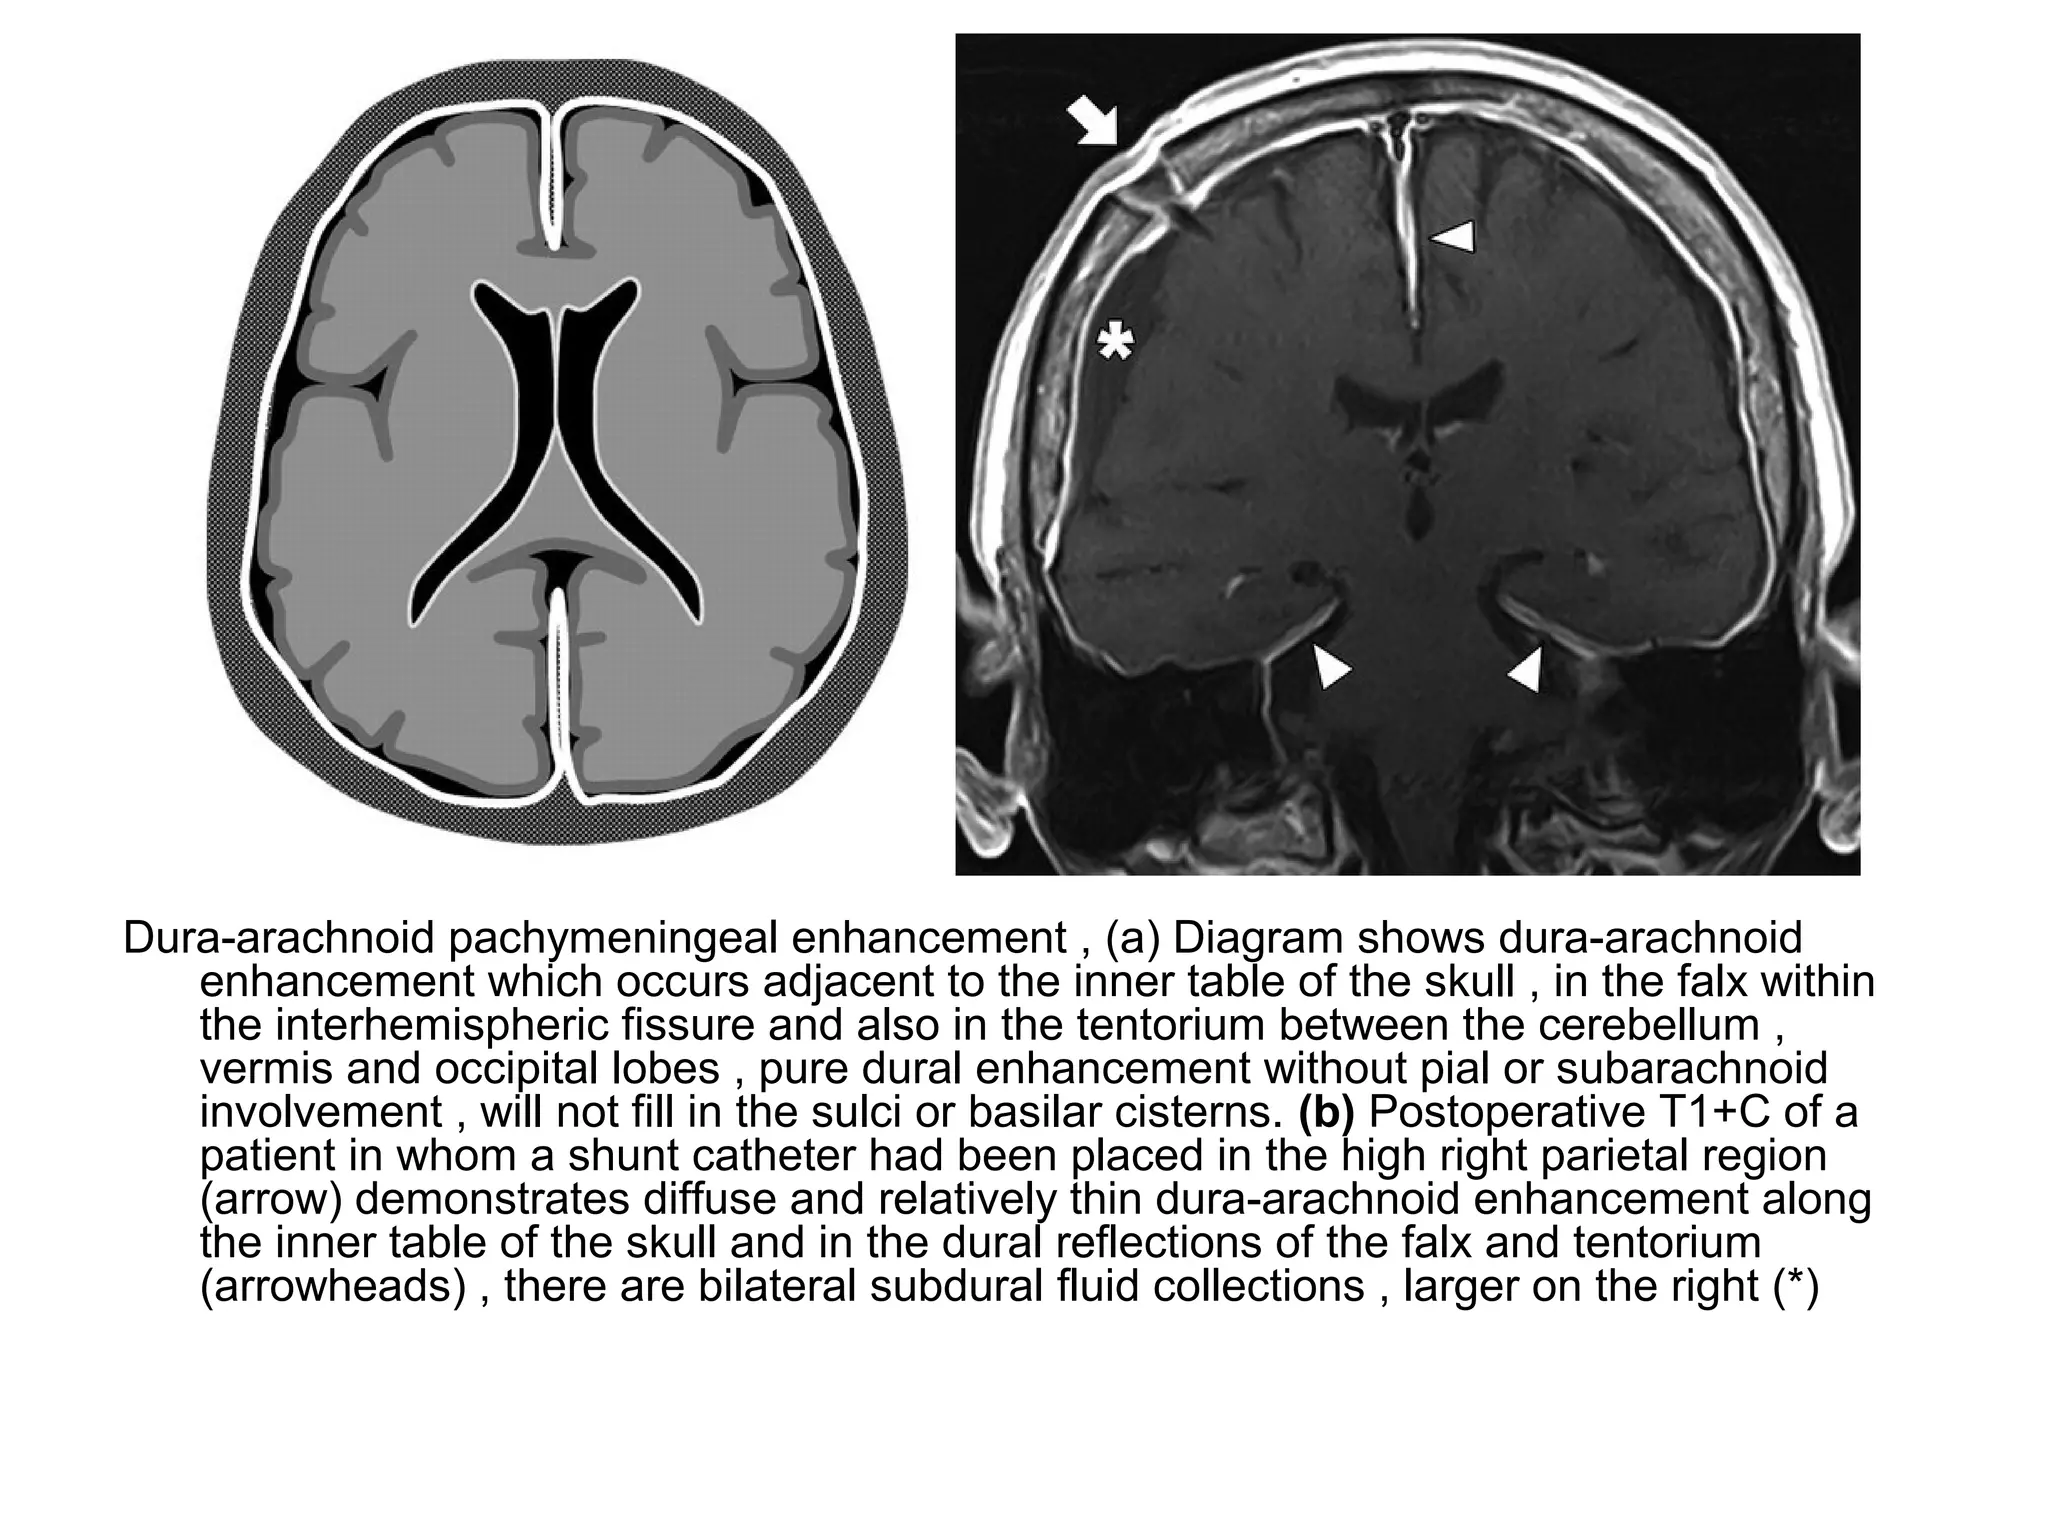

Dura-arachnoid pachymeningeal enhancement , (a) Diagram shows dura-arachnoid

enhancement which occurs adjacent to the inner table of the skull , in the falx within

the interhemispheric fissure and also in the tentorium between the cerebellum ,

vermis and occipital lobes , pure dural enhancement without pial or subarachnoid

involvement , will not fill in the sulci or basilar cisterns. (b) Postoperative T1+C of a

patient in whom a shunt catheter had been placed in the high right parietal region

(arrow) demonstrates diffuse and relatively thin dura-arachnoid enhancement along

the inner table of the skull and in the dural reflections of the falx and tentorium

(arrowheads) , there are bilateral subdural fluid collections , larger on the right (*)